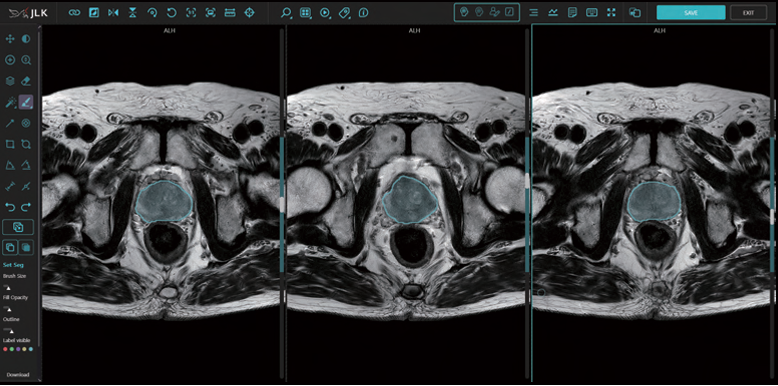

이번 승인으로 AI 기반 전립선 MR 영상 분석, PIRADS 진단, PSA(전립선 특이 항원) 밀도 진단 등 전립선암 진단에 필요한 모든 데이터를 제공하는 메디허브 프로스테이트의 기술적 우수성을 다시 한번 증명했다는 설명이다.